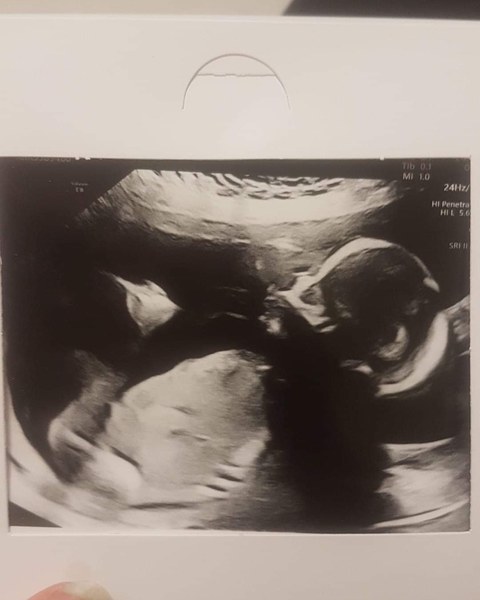

Just had my 20 week scan and little man looks absolutely perfect.

Sonohrapher gave me a fright when she said she would guess a girl, then he opened his legs and she was like no no that's 100% a boy hahaha.

Just waiting for blood test results then i can go home. I was so anxious for this scan as it's so detailed and I just want him to be healthy.

Here's my boy, he has his mouth open, he's absolute perfection I love him so much Smile

Lovely looking Scan InOmniaParatus13. Did he wave for you? Hope the blood tests don't take too long. At mine they make you wait around 2 to 3 hours after the scan just to take blood.

@quirkyquichie thank you! He didn't wave but he was covering his face then decided to turn to face me and move his hands so I got to see his gorgeous face!